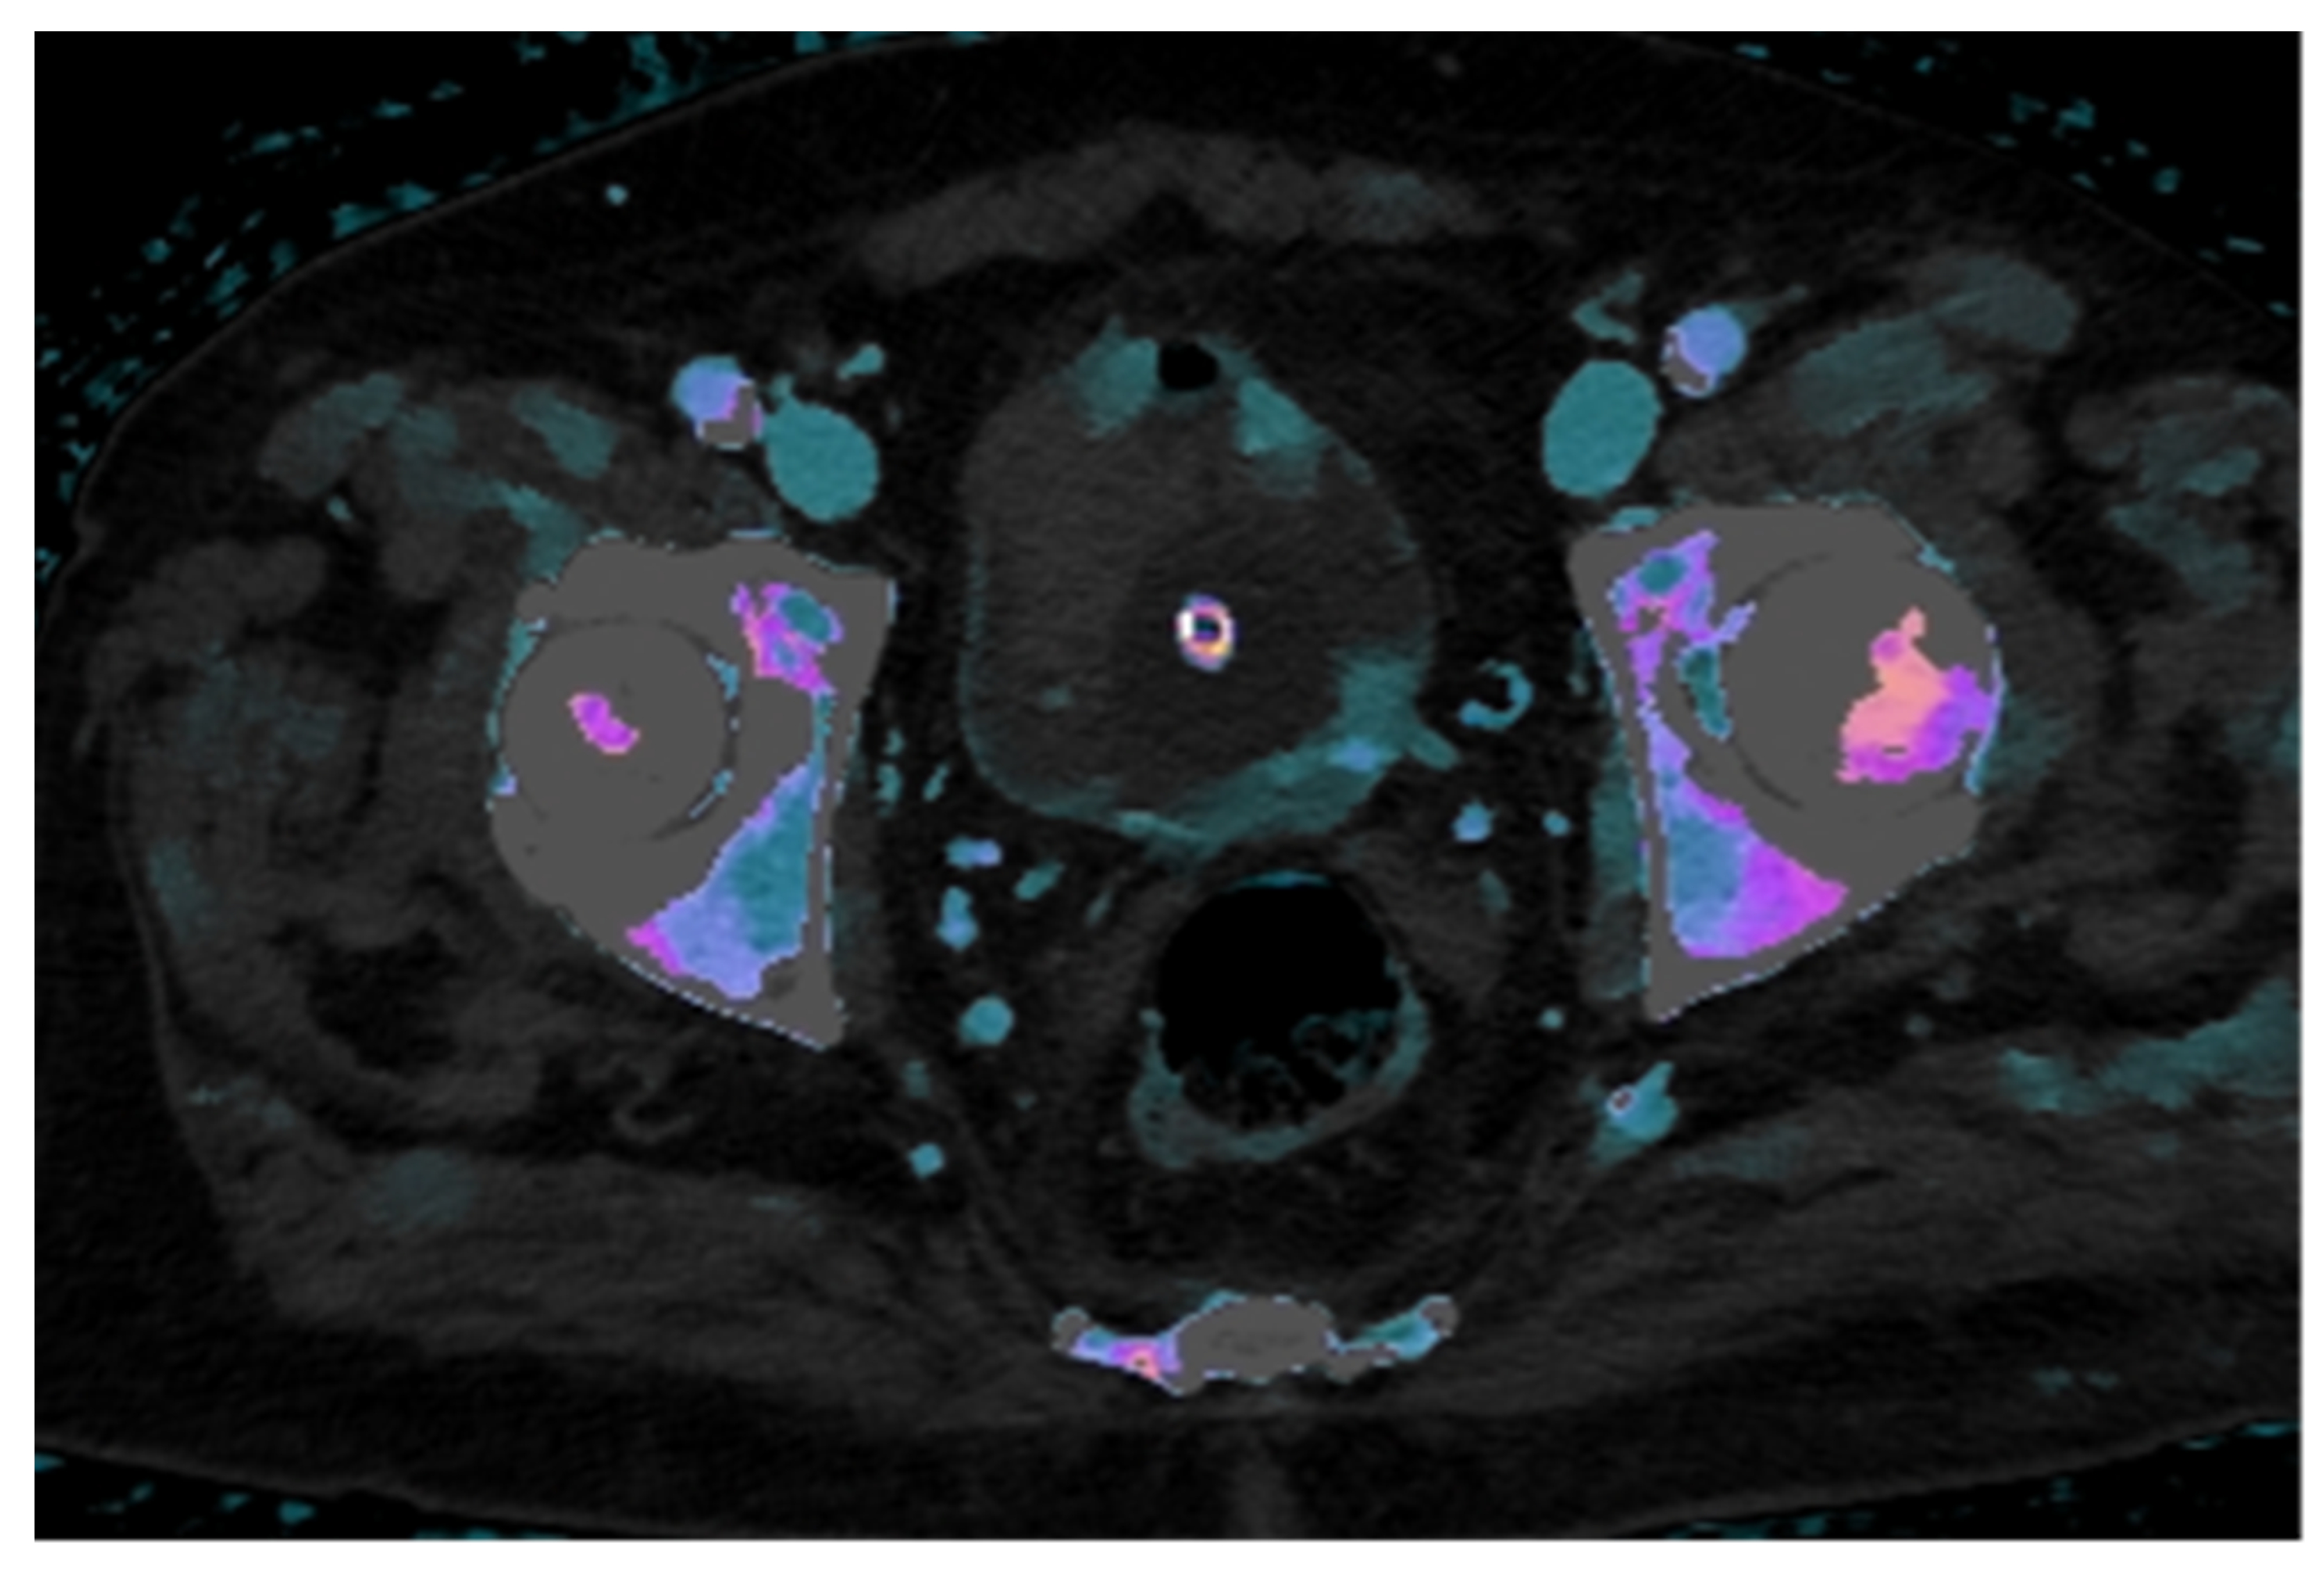

In this case, the iodine map overlaid on the conventional venous phase image demonstrates clear increased iodine uptake in two foci along the left posterolateral bladder wall and in two minute foci along the anterior wall, findings consistent with hypervascular neoplastic tissue. In contrast, the intraluminal hyperdense mass, visible on the unenhanced scan, shows no significant iodine uptake, supporting the diagnosis of a non-enhancing structure, most likely a thrombus (Figure 3).

Figure 3. The iodine density map overlaid on venous phase CT images shows increased iodine uptake in the posterolateral left bladder wall and in two foci of the anterior wall, findings indicative of metabolically active neoplastic areas. In contrast, the mass in the right anterolateral wall demonstrates no iodine uptake, consistent with a non-metabolically active lesion, suggestive of thrombus.